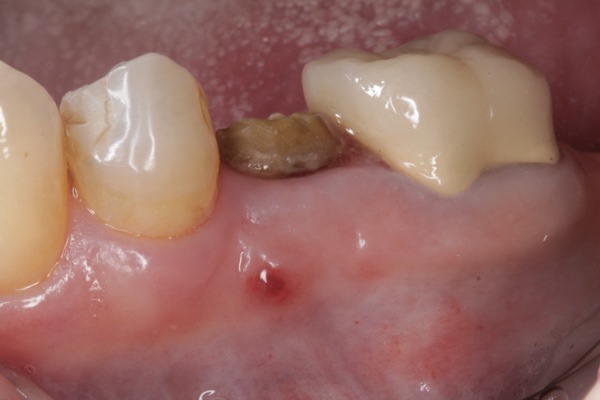

Fig 8. At 4 weeks postoperative, the barrier has been removed, exposing osteoid tissue.

Figure 8

Fig 9. At 8 weeks postoperative, the ridge was keratinized.

Figure 9

Fig 10. At 3 months postoperative, the flap was elevated, demonstrating a restored buccal plate of bone.

Figure 10

Fig 11. An implant was placed in regenerated bone.

Figure 11